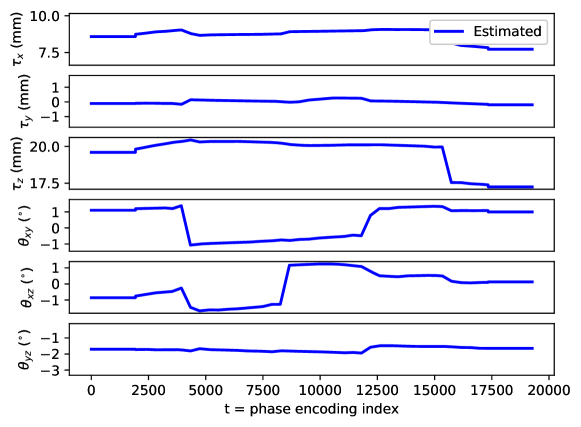

Appendix C Motion parameter estimation

The proposed motion correction algorithm described in Section 2 estimates the rigid motion that the object of interest undergoes during the scan, in order to undo its effect on the reconstructed 3D image. In 3D, the rigid motion is performed by: a plane rotation in the corresponding plane , a plane rotation in the plane, a plane rotation in the plane, a translation in the direction, a translation in the direction, and a translation in the direction (in this order). We adopt the following convention: the direction corresponds to the left-right direction, to the posterior-anterior direction, and to the inferior-superior direction, the plane corresponds to the axial plane, to the coronal plane, and to the sagittal plane. Left/right, anterior/posterior, and inferior/superior are meant from the patient perspective. The orientation of the rotation planes is determined by the right-hand rule.

By design, the prospectively-induced motion for all the experiments detailed in Section 3 follows a step-wise behavior (each step corresponding to a change of pose). In this appendix, we gather the estimated rigid motion parameters for the results shown in Section 4, as a function of time. As noted in the main body of the paper, time is equated to the phase-encoding plane coordinate index, ordered by the corresponding acquisition ordering. We display the estimated motion parameters in Figure 19 (see Sections 3.1, 4.1, Figure 2), Figure 20 (see Sections 3.1, 4.1, Figure 4), Figure 21 (see Sections 3.1, 4.1, Figure 6), Figure 22 (see Sections 3.2, 4.2, Figure 10), Figure 23 (see Sections 3.3, 4.3, Figure 12), and Figure 24 (see Sections 3.3, 4.3, Figure 14).